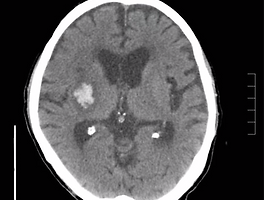

| BG ICH (0) | 2021.07.12 |